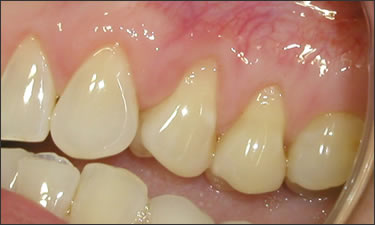

This mouth had recession on just one tooth with very little bone to support the tooth. The area needed support and thickness. The tissue was placed and the area now has thicker tissue to withstand the forces that the patient needs to place on it.